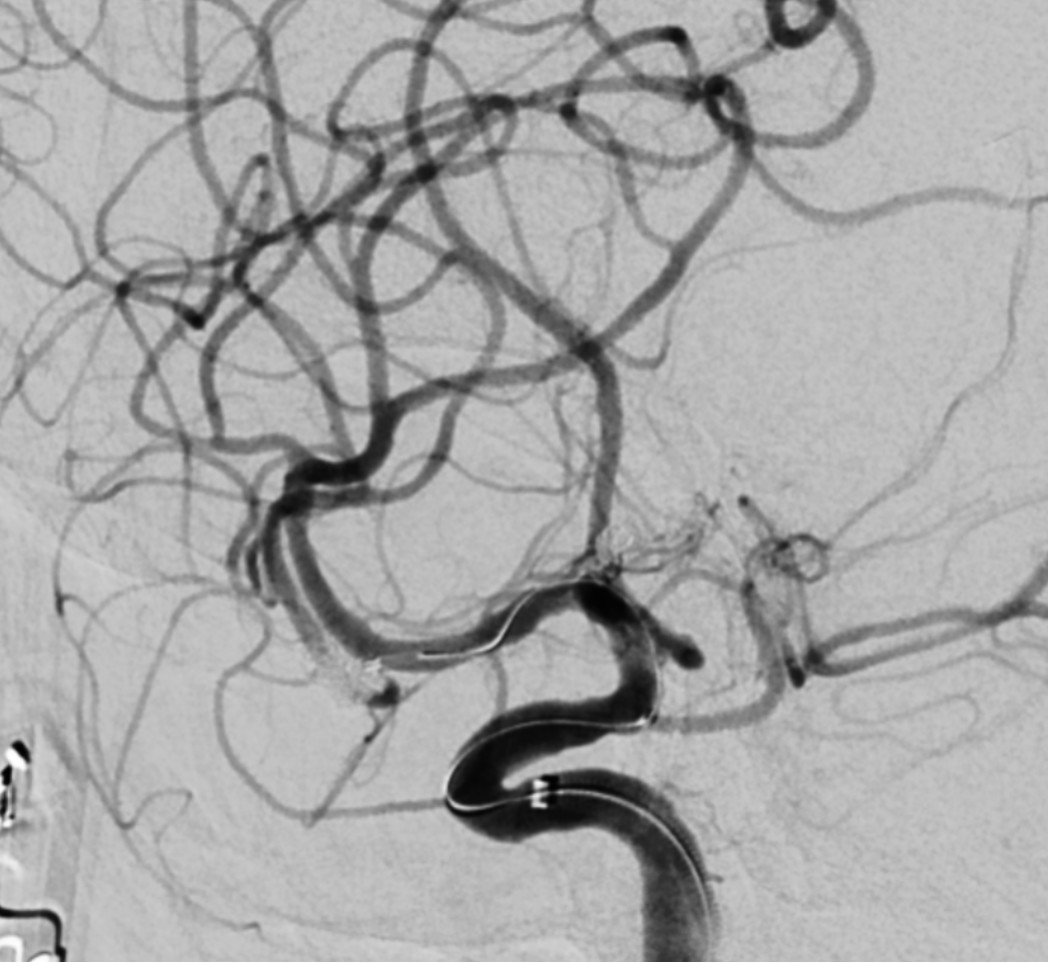

术后再次进行造影,此时显示动脉瘤瘤颈夹闭完全,大脑中动脉下干管腔无狭窄,前向血流满意。

术后造影